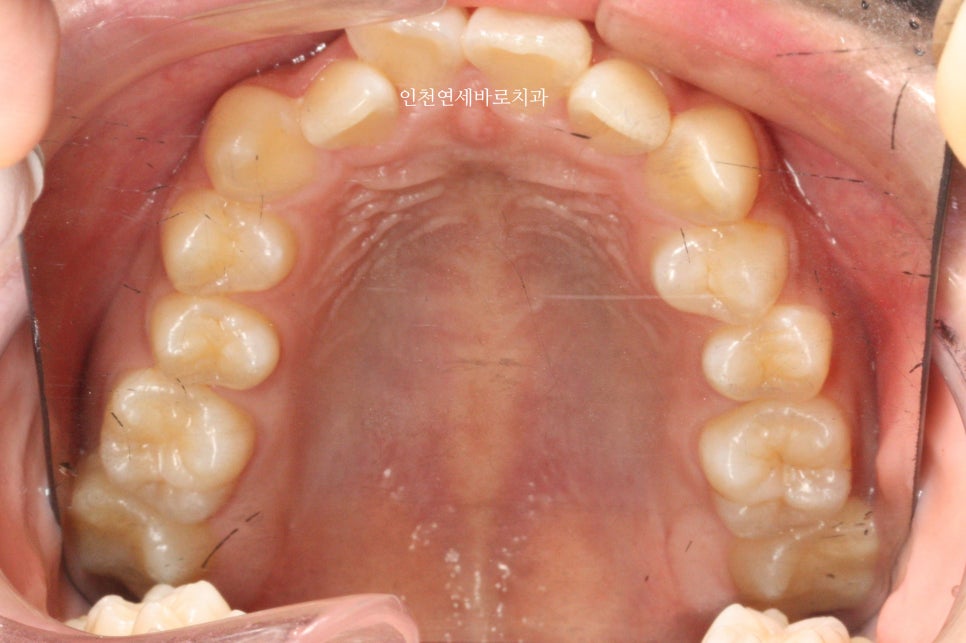

위아래 덧니가 있었고, 깊이 물리는 과개교합 및 중심선의 불일치 보이고 있습니다.

덧니를 비발치로 해결하면서 입술도 후방이동하기로 했습니다.

미니스크류를 총 6개 식립했던 환자분입니다.

골격에 대한 분석 후 위쪽 치열은 후방 + 상방 으로 당겼습니다.